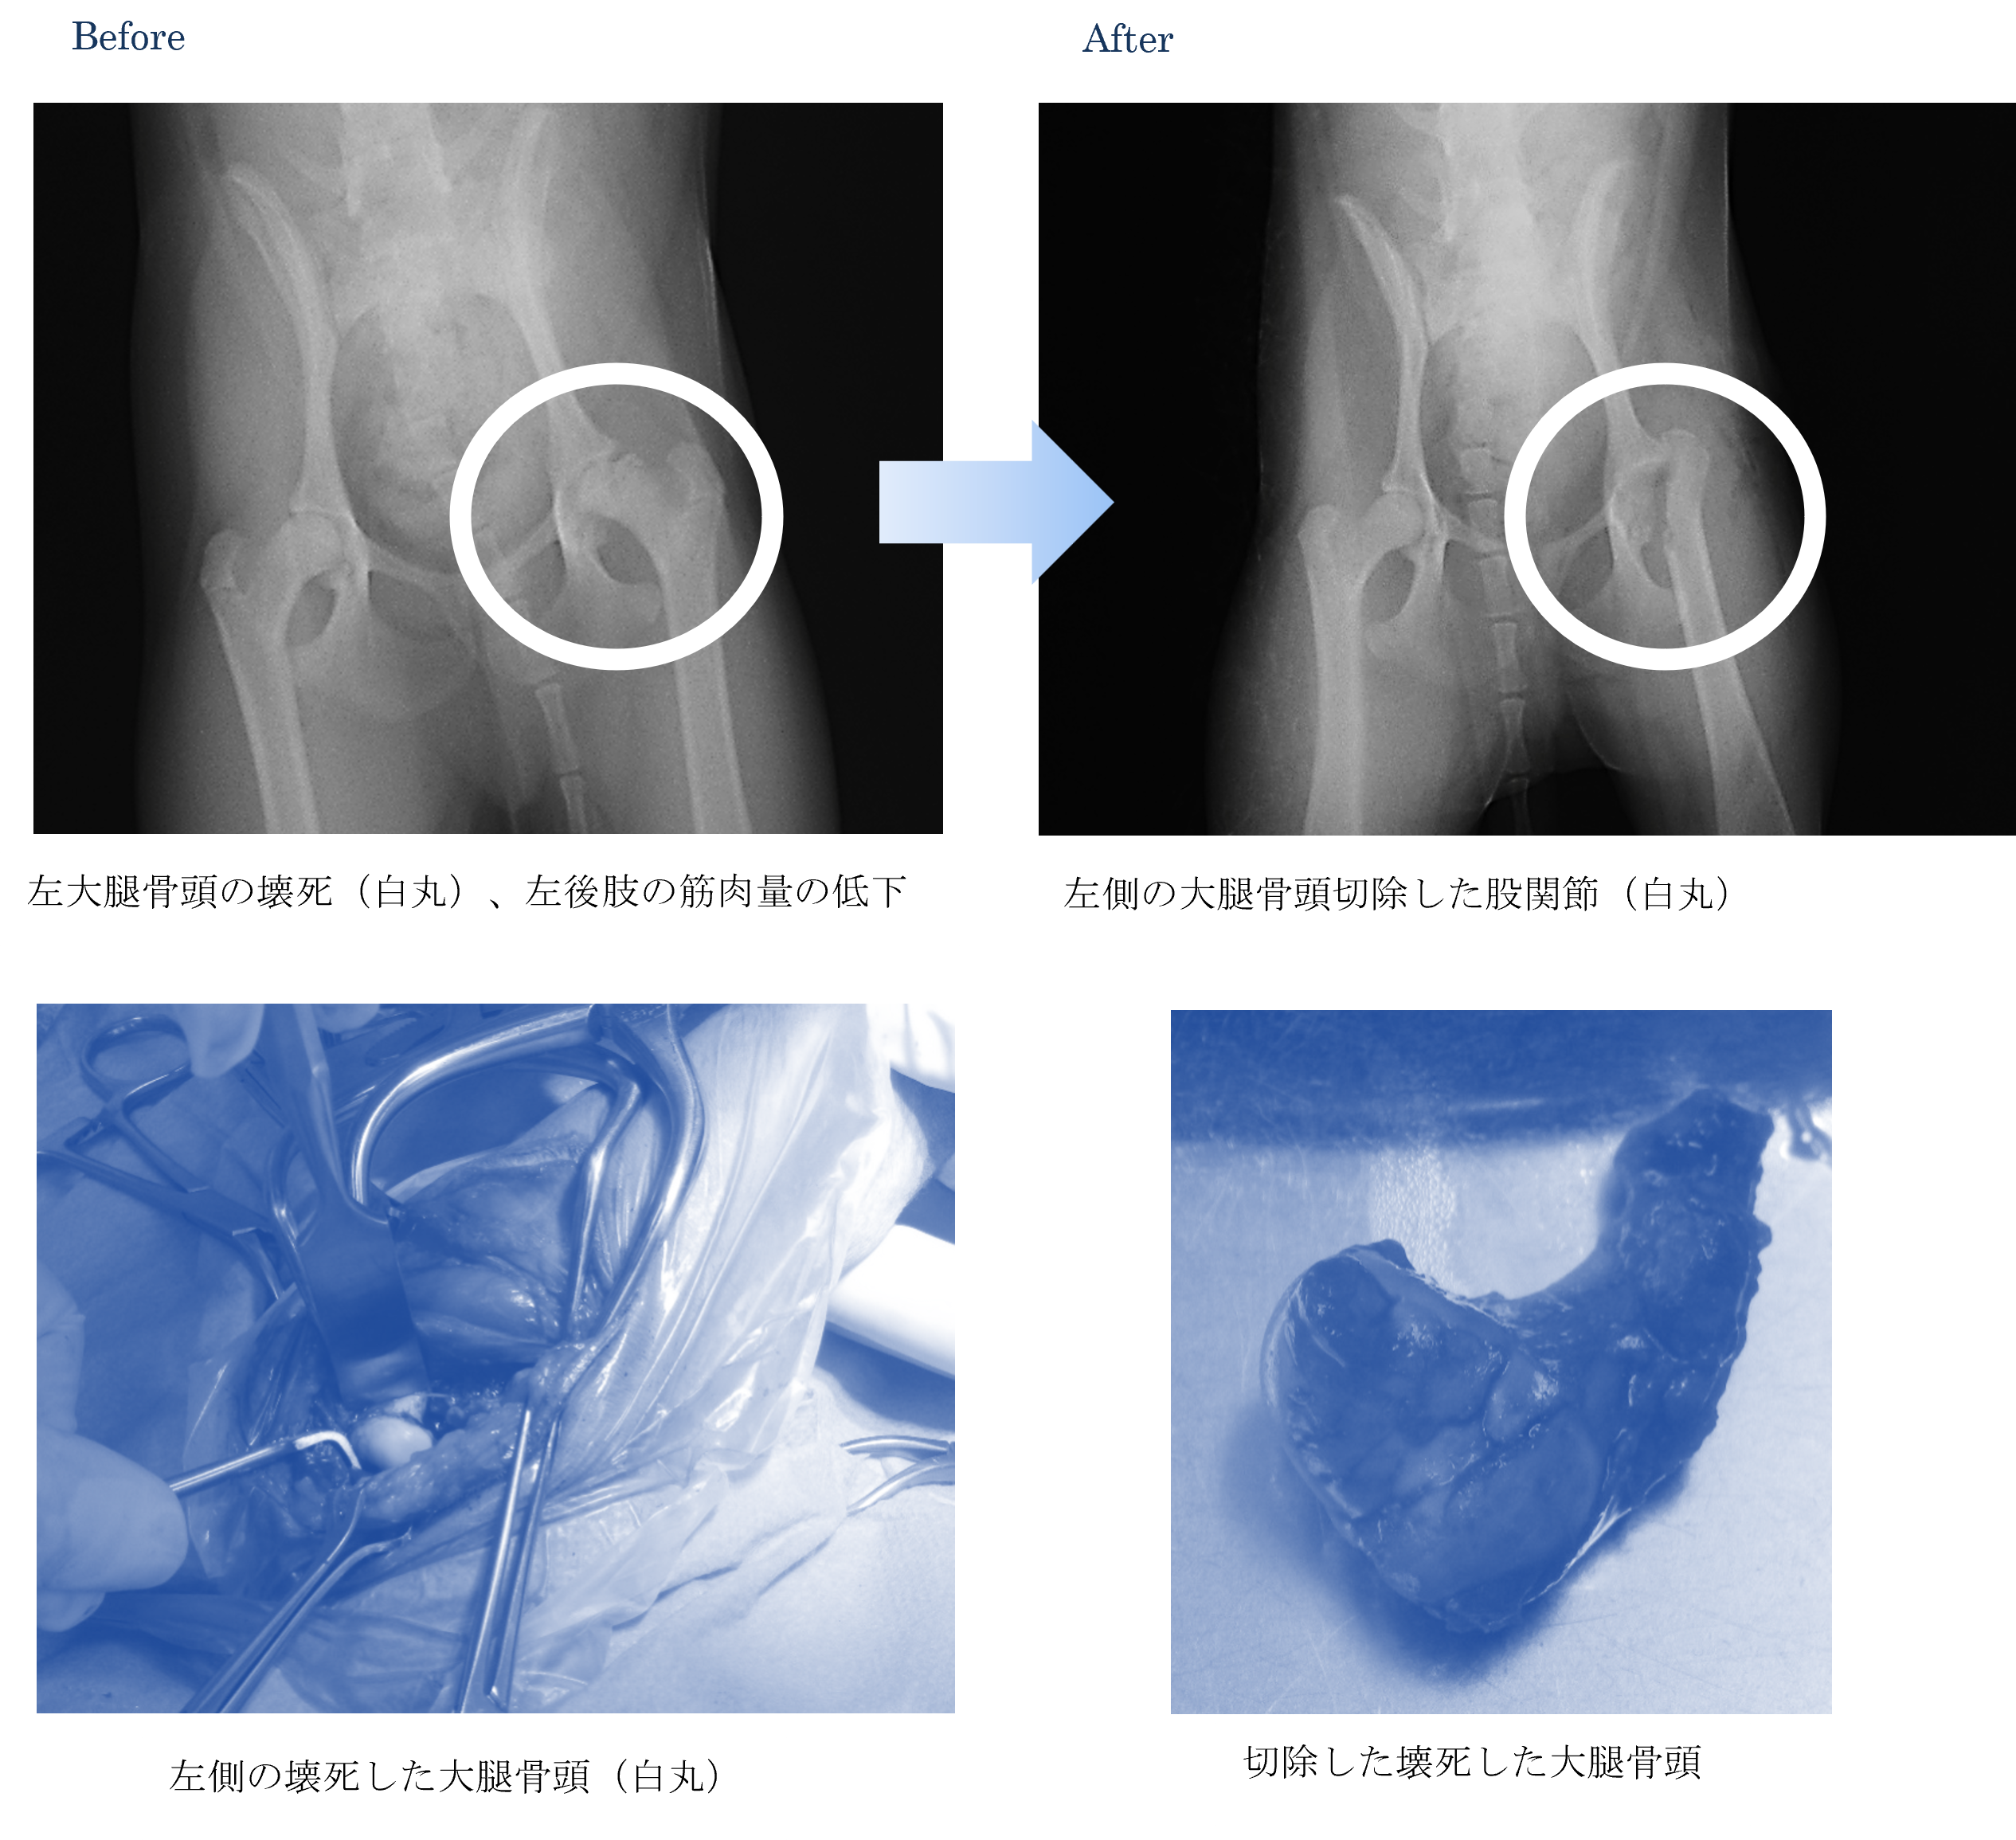

各種検査より、大腿骨頭壊死(レッグ・ペルテス)と診断しました。

ご家族と相談した結果、手術による大腿骨切除術をすることになりました。

術後はリハビリを行い、以前よりも元気に走れるようになりました。